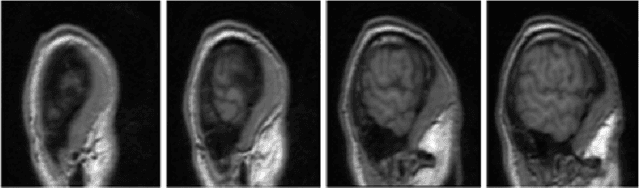

Brain extraction or skull stripping is a fundamental procedure in most of neuroimaging processing systems. The performance of this procedure has had a critical impact on the success of neuroimaging analysis. After several years of research and development, brain extraction still remains a challenging problem. In this paper, we propose an effective method for skull stripping in Magnetic Resonance Imaging (MRI) scans named ASM-CNN. Our system is a combination of Active Shape Model (ASM) and Convolutional Neural Network (CNN), taking full advantage of these two methods to achieve remarkable results. Instead of working with 3D structures, we process 2D image sequences in sagittal plane. First, we divide images into different groups such that, in each group, the shapes and structures of brain boundaries have similar appearances. This allows developing precise algorithms for each group in order to produce high performance segmentation results. Second, a modified version of ASM is used to detect the brain boundary in images by utilizing prior knowledge of each group. Finally, CNN and the post-processing methods such as Conditional Random Field, Gaussian Process and some special rules are applied to refine segmentation contour produced by ASM. We compared ASM-CNN with the latest version of five state-of-the-art, publicly available methods, namely BET, BSE, 3DSS, ROBEX and BEAST. The evaluation was carried out by using three public datasets IBSR, LPBA and OASIS. The experimental results show that the proposed method outperforms five states-of-the-art algorithms, surpassing all the other methods by a significant margin in all experiments.